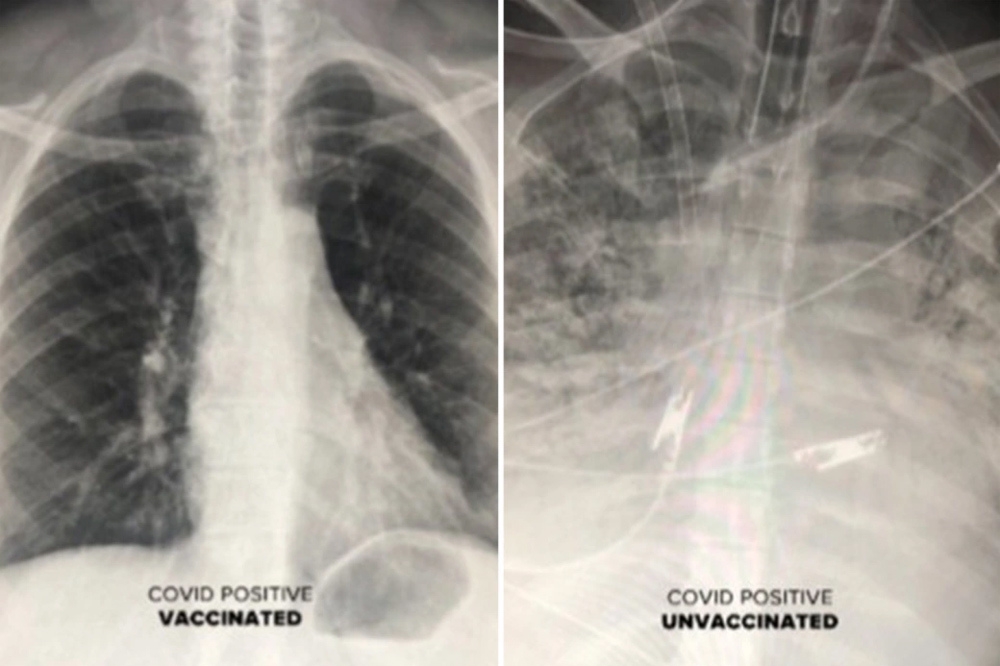

| Phim chụp phổi của người đã tiêm vắc xin (trái) không bị trắng xóa như người chưa tiêm vắc xin (phải) |

Bác sĩ Durrani cho biết, phim chụp phổi của những bệnh nhân Covid-19 từng được tiêm chủng cho thấy không khí lưu thông nhiều hơn. Trên hình, phần lớn phổi có màu đen, nghĩa là có rất ít hoặc không có tổn thương nào.

Ngược lại, phim chụp của một người không được tiêm chủng cho thấy phổi bị tắc nghẽn, hạn chế lưu lượng oxy đi khắp cơ thể.

Tiến sĩ Durrani cho biết: “Nếu một người đã được tiêm vắc xin vẫn nhiễm Covid-19 (nhiễm trùng đột phá), họ có thể bị khó thở. Dù những ca nhiễm trùng đột phá dẫn đến viêm phổi, kết quả chụp CT của họ vẫn không tệ như bệnh nhân chưa được chủng ngừa”.

Với hình ảnh cho thấy sự tàn phá mà virus SARS-CoV-2 có thể gây ra trong phổi, Tiến sĩ Durrani khẳng định: “Vắc xin đang hoạt động cực kỳ hiệu quả và ngăn không cho virus gây ra viêm phổi hoặc xâm nhập vào phổi”.